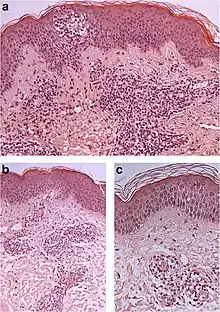

Spongiotic dermatitis

It is characterized by epithelial intercellular edema.[2]

| Generally/Not otherwise specified[notes 2] | Typical findings:[2]

Typical findings:[2]

Typical findings:[2]

PAS stain is essential to exclude fungal infection.[2] |

Subacute Subacute |

| Allergic/contact dermatitis or atopic dermatitis | As above. Eosinophils may be present in the dermis and epidermis (eosinophilic spongiosis).[2] |  Allergic dermatitis Allergic dermatitis |

.jpg.webp) Atopic dermatitis Atopic dermatitis | ||

| Seborrheic dermatitis | Typical findings:[5]

Typical findings:[5]

Typical findings:[5]

In addition to above, an unspecific spongiotic dermatitis can be consistent with nummular dermatitis, dyshidrotic dermatitis, Id reaction, dermatophytosis, miliaria, Gianotti-Crosti syndrome and pityriasis rosea.[2][notes 2]